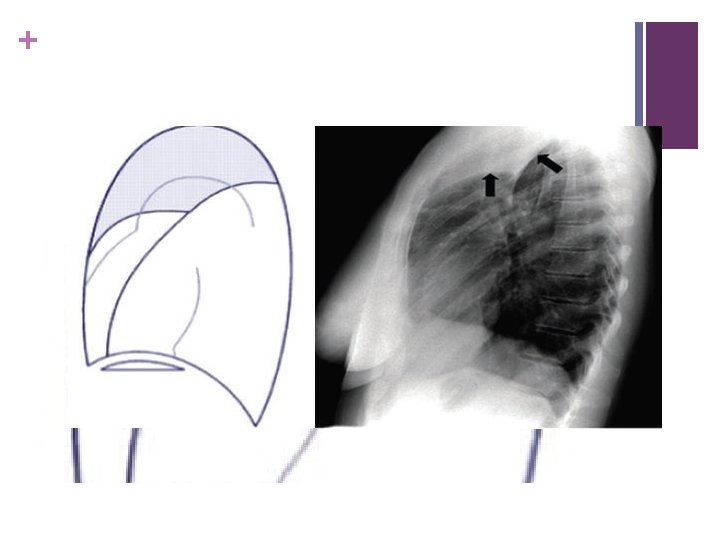

+ RUL collapse –elevation Rt hilum, horizontal fissure